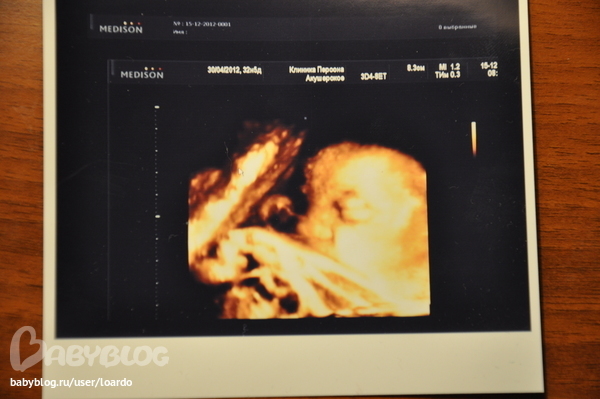

Узи в 32 недели +фото!

Результаты: УЗИ, КТГ, доплера, скринингаСходили мы на узи, после того как пролежали 2 недели в род доме с угрозой, ну вообщем все у нас хорошо) Девочка моя идет ровно по сроку пдр от месячных , весим мы 2020, не маленкие) В род доме ставили раскрытие шейки, рассказала узистке, она прям приобалдела, говорит, тебя бы от туда и не выпустили,так что ко всему еще и посмотрела шейку вагинально,раскрытия нет, просто она мягкая очень! Очень хорошо, я довольна была,муж тоже,офигевал все смотря на экран,говрит все пальчики пересчитал, сказал все ок))))юморист! Сделали нам фото, оцените, муж сказал что на меня похожа и щечки такие же и нос картошкой)

По фото ничегошеньки не понятно...

Представляешь, вообще не могу разобрать, где нос, где щечки)))) сама хороша! Выглядишь отлично!

Аааа ну ты что))))сверху справа голова чуть меньше пол лица закрывает рука!!!! у руки еще косточка видна! спасибо, ну выгляже не очень большая все таки)

Выглядишь отлично!!! и волосы такие блестящие!!! и ножки стройные! пузик подрос, хороший такой)) жалко я на этих снимках не понимаю ничего(( ну и главное что все хорошо у вас, молодцы!

Какая уже большая малышка! носики у вас и правда похожи! а выглядишь ты замечательно, никакой не слоненок, ты слонят не видела :))) вот у нас на работе девочка в 7 месяцев уже с таким животом была, раза в полтора больше чем у тебя. Все думали, что двойня :)

блин а ятак все отчетливо вижу))))мамочка!